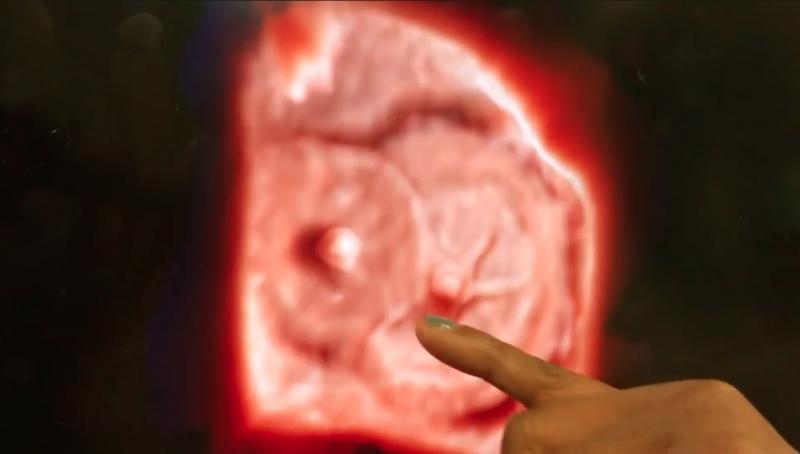

This is an example of an arterial venous malformation (AVM) in the brain imaged on a Canon Alphenix Alpha angiography ...